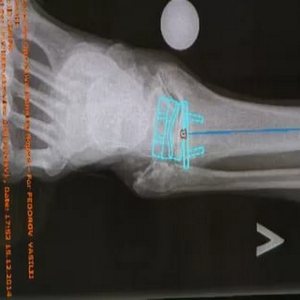

Для выполнения эндопротезирования пациента размещают, лежа на спине, со слегка приподнятыми бедрами. На проксимальной части бедра накладывается жгут для ограничения кровотока. По центральной линии сустава выполняется разрез длиной 10 см, чтобы раскрыть анатомические структуры. Происходит осмотр сустава, поиск нервов и сухожилий для того, чтобы защитить и не травмировать их во время вмешательства.

Одновременно производится очистка остеофитов, исправление других дефектов, которые могут влиять на нестабильность голеностопа. В зависимости от естественного угла голеностопного сустава (варусная или вальгусная) большеберцовая кость может располагаться медиально или латерально. При установке протеза производится резекция, чтобы выровнять голень относительно стопы.

После исправления костей сустава и выравнивания лодыжек, проверяются другие компоненты для поддержания стабильности. При ограничении разгибания стопы требуется работа над ахилловым сухожилием. Проводится реконструкция связок на латеральной и медиальной сторонах лодыжки. При плоско-вальгусной деформации проводится подтаранный артроэрез.